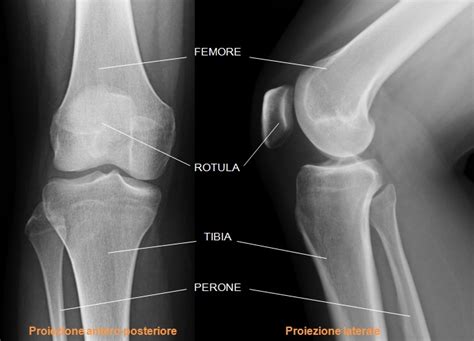

- Radiologia Convenzionale (RX): Le radiografie sono lo strumento principale per visualizzare i depositi di calcio nelle cartilagini articolari. Si possono osservare calcificazioni lineari e sottili, dette lamellari, o più grossolane, come nei menischi. Queste lesioni sono frequentemente riscontrabili nei polsi, nella sinfisi pubica, nelle spalle, nelle anche e, più raramente, in articolazioni di minori dimensioni.